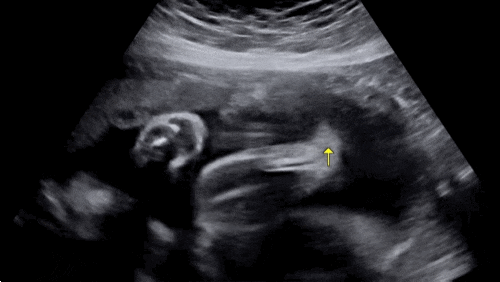

?30주차 증상? 1) 처음으로 엘디한테 갈비뼈쪽 맞은 날!! 진짜 “억!” 소리가 나는데.. 눈이 땡그래...